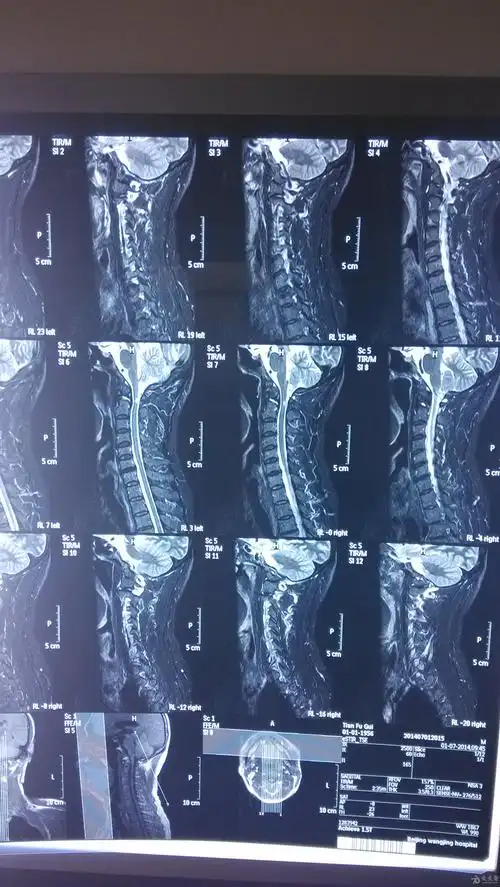

请大神们看个颈椎病的片子